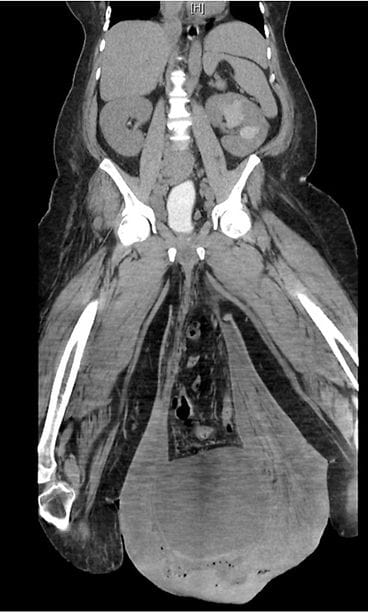

Sairaalaan saapuessaan miehen kivespussi roikkui jo polvien kohdalla. Lisäksi kivespussin iho oli paksuuntunut ja siinä oli märkiviä avohaavoja, joista tihkui ulos pahanhajuista nestettä.

Tutkimuksissa lääkärit löysivät miehen sisuksista suuren tyrän. Hoitamaton tyrä oli johtanut lymfedeemaan, imunestekierron häiriöön, joka paheni asteittain.

Miehellä diagnosoitiin Fournier’n gangreeni, joka on kuolioita aiheuttava bakteeritulehdus miehen genitaalialueella. Verenmyrkytyksen ja lihan mädäntymisen riskin vuoksi potilas vietiin nopeasti leikkaussaliin.

Leikkauksessa kirurgit poistivat kivespussista tulehtunutta ihoa ja löysivät ihonalaisista rasvakudoksista kuolioita sekä lisää haavoja. Viisi päivää leikkauksen lääkärit joutuivat poistamaan miehen kivespussit. Lopputuloksen voit katsoa tapausraportista. Varoitus: Raportin kuvat voivat järkyttää.